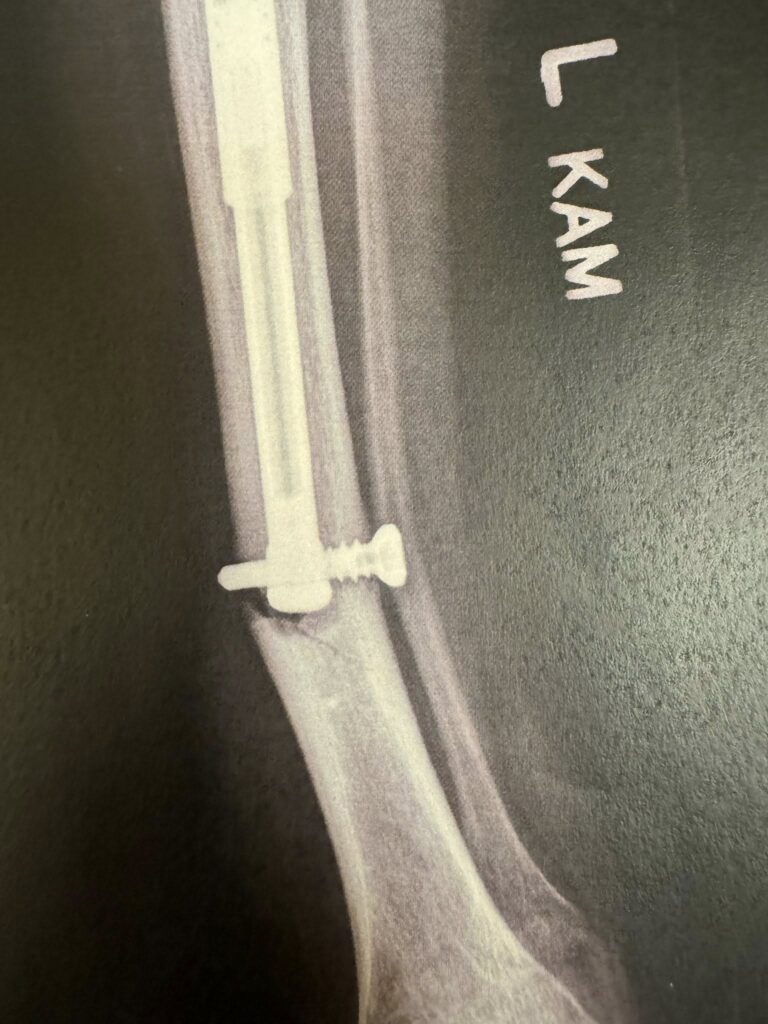

Gabriel “Gabe” Acuna was born the same year (2011) the Avs drafted Gabriel “Gabe” Landeskog. Young Gabe was born with a left leg substantially shorter than his right and missing several toes. In 2012, the same year Landy became captain of the Avalanche, Dawg Nation was blessed to present a check to the Acuna’s to help offset some of Gabe’s medical bills. What happened next is nothing short of miracle, and honestly mirrors Landy’s equally amazing story.